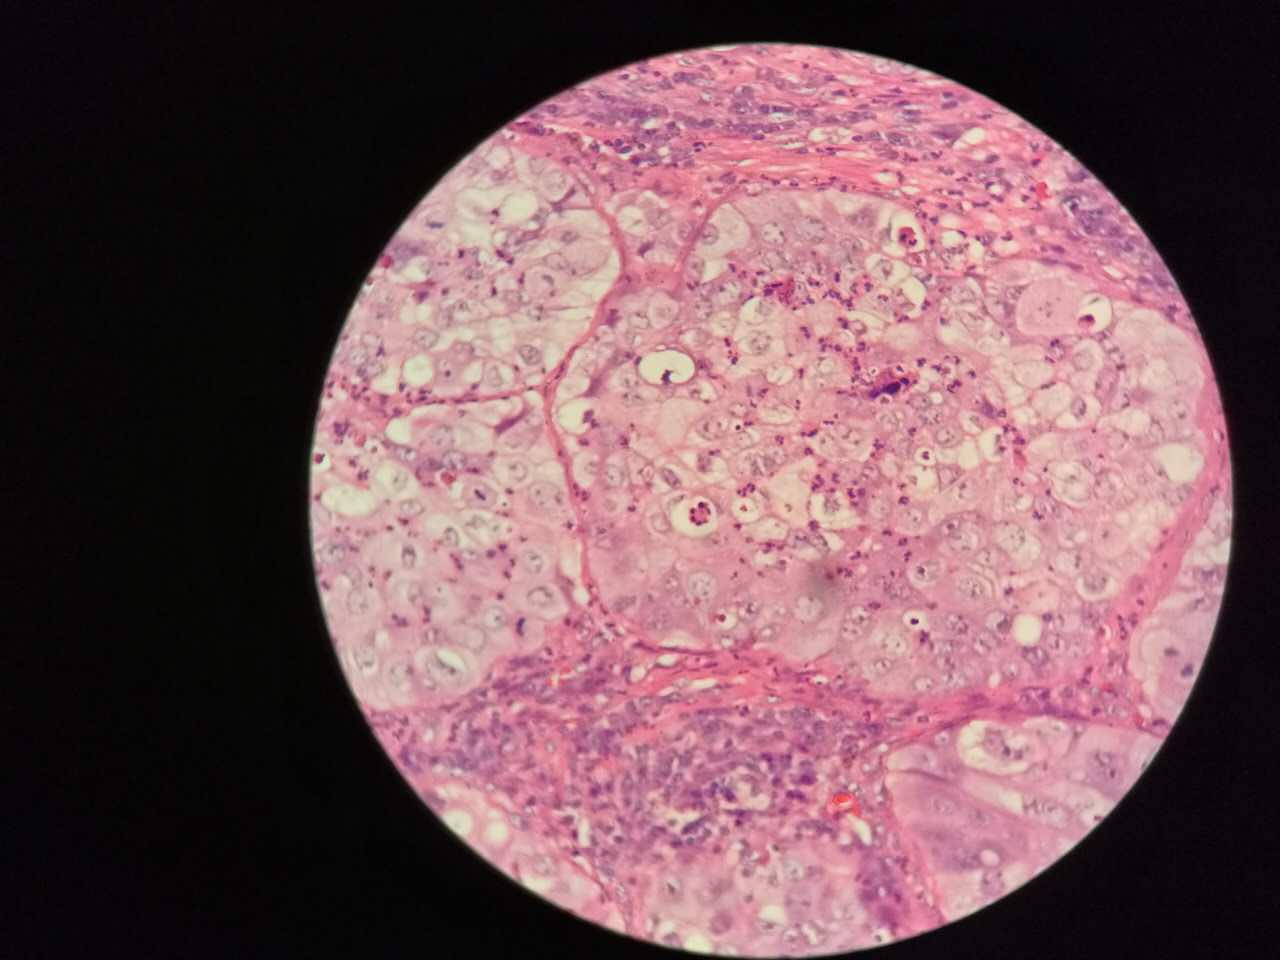

这个是早期结节状的粘液型腺癌

随着粘液近距离播散

早期粘液漂散也是近距离的,右侧肺泡里干净,没粘液,粘液产量有限,并且互相有黏连牵制。

所以结节性粘液腺癌边界一般较清楚

粘液型腺癌的肿瘤细胞排列整齐,核位于基底,细胞呈柱状。

肺泡间隔(间质)经常比较细

差不多都长这样

这个生长密集,相对要重

这个细支气管,一半癌浸润

肿瘤细胞形态仍然相似

中央有个肺血管,说明破坏力不强

也会有些坏死,连同粘液咳出去,就形成实变区内的空洞